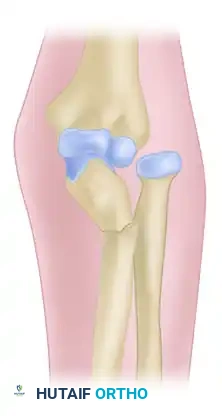

Figure 57-79: Diagrammatic representation of an Essex-Lopresti fracture-dislocation demonstrating radial head fracture, interosseous membrane rupture, and subsequent proximal radial migration.

The tethering effect of the proximal radial-oriented fibers of the interosseous membrane is lost. If the radial head is resected or fails to provide a proximal buttress, rapid proximal migration of the radius occurs. This catastrophic collapse results in severe wrist pain from ulnocarpal impingement and elbow pain from radiocapitellar impingement.

The Essex-Lopresti lesion is a severe longitudinal radioulnar dissociation (LRUD) characterized by a triad of injuries: a fracture of the radial head or neck, disruption of the distal radioulnar joint (DRUJ), and tearing of the interosseous membrane (IOM) for a considerable distance proximally.

This injury typically results from a high-energy fall on an outstretched hand. The axial load transmits through the carpus to the radius, fracturing the radial head. As the radial head fails, the energy propagates proximally to distally, rupturing the central band of the interosseous membrane and ultimately disrupting the DRUJ ligaments.